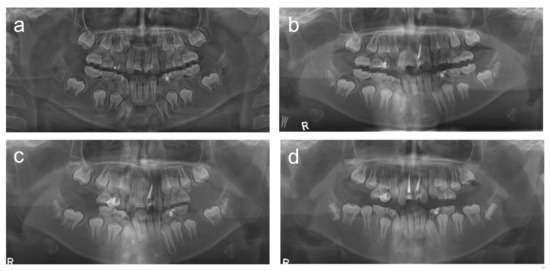

2.1. Case 1

2.2. Case 2

2.3. Case 3

2.4. Case 4